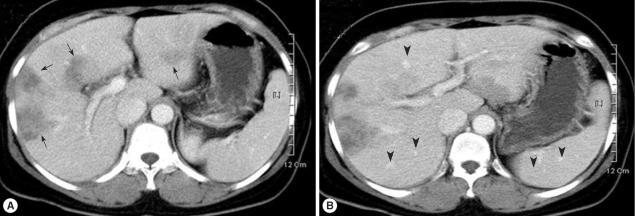

Contrast-enhanced abdominal CT scan revealed duodenal diverticulum and ascites in the pelvic cavity (data not shown) and most importantly, multiple hypodense inflammatory lesions with irregular margins and amorphous shapes in the right lobe of the liver (Fig. 1). Mild but diffuse dilatations of intrahepatic bile ducts were also observed. Considering the morphology and size of the lesions, the patient was suspected to be mixed-infected with Fasciola sp. and C. sinensis. Abscess suspected to be formed by an amebic infection was also observed at the lower tip of the liver (data not shown). Serological tests by micro-ELISA were positive for cysticercosis, clonorchiasis, and fascioliasis (Table 1). Eggs of C. sinensis and trophozoites of E. histolytica were found in stool examinations.

Fig. 1

Abdominal CT scan of the patient. (A) Contrast enhancement using iodine dye revealed multiple inflammatory lesions (arrows). (B) Dilatations of intrahepatic bile ducts (arrow heads) are seen in the liver parenchyme.

Fig. 1 Abdominal CT scan of the patient. (A) Contrast enhancement using iodine dye revealed multiple inflammatory lesions (arrows). (B) Dilatations of intrahepatic bile ducts (arrow heads) are seen in the liver parenchyme.